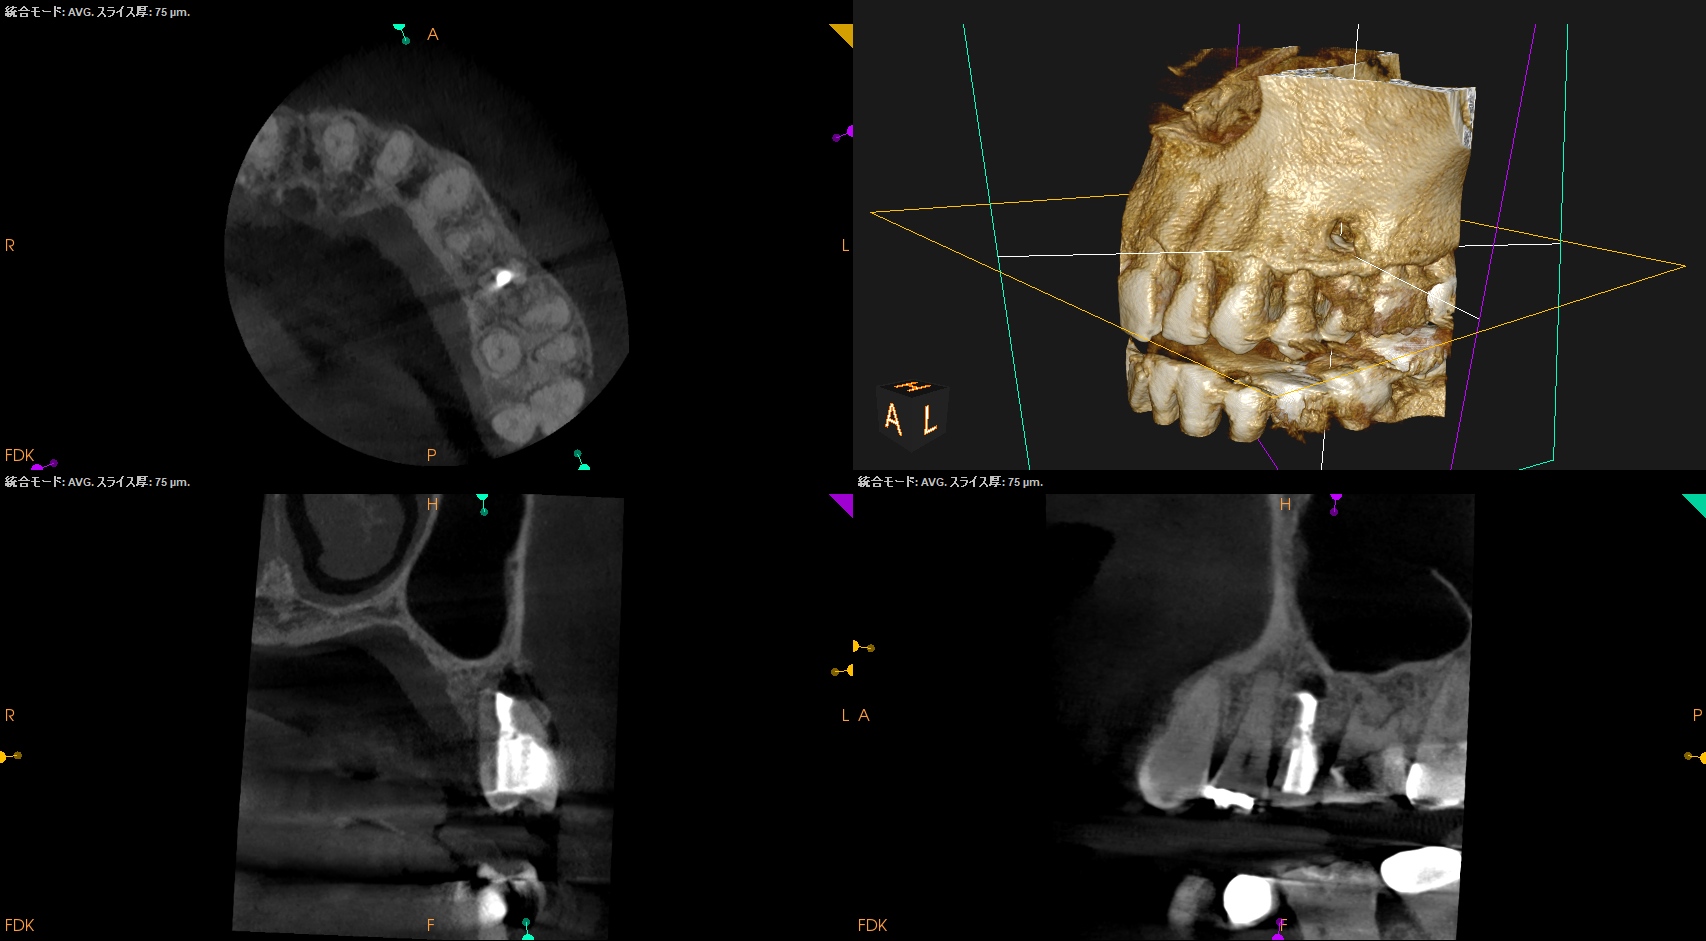

当該部位をOsteotomyした。

Retroprepした。

脱離した逆根管形成窩洞の中に肉芽が紛れ込んでいた。

これを逆根管形成で除去しつつ、問題がないことを確認した。

Retrofillした。

術後にPA, CBCTを撮影した。

再度、何らかの原因で逆根管充填材が外れないように深く逆根管充填した。

今回の修正は、

逆根充材の厚みを増してみるというその1点のみである。

やはり浅い逆根管充填はそれが外れやすいというリスクがあるようだ、と私はこのケースから感じた。